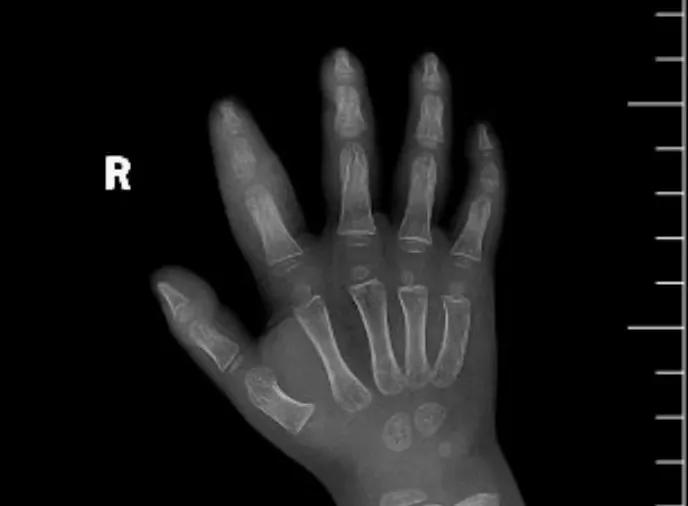

近日,市二院顯微外科接診一名3歲半的小患者,被玉米葉割傷右食指,因家長(zhǎng)疏忽大意,導(dǎo)致一個(gè)小小的傷口竟然發(fā)展成了骨髓炎。來(lái)院時(shí)患兒右食指腫脹明顯,既不能伸也不能彎,皮膚發(fā)燙,疼得哇哇大哭。

第三天開(kāi)始,月月哭鬧不止,一直說(shuō)手疼,怎么哄也不行,于是在當(dāng)?shù)蒯t(yī)院治療了10來(lái)天,然而月月的手指依然腫得像個(gè)胡蘿卜,疼痛感依然存在。此時(shí),月月的媽媽才覺(jué)得事情不大對(duì)勁,于是經(jīng)過(guò)打聽(tīng),慕名來(lái)到市二院顯微外科。入院后,經(jīng)檢查發(fā)現(xiàn),月月的右食指骨質(zhì)有侵蝕,骨骺有缺損,甚至?xí)绊懸院笫种傅陌l(fā)育。聽(tīng)到這個(gè)消息,月月媽媽感覺(jué)心都揪住了。